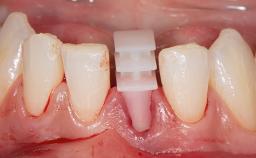

Immediate Implant Placement and Restoration of a Maxillary Left Central Incisor with a Provisional Crown

Leon Pariente and Karim Dada outline the Immediate Implant Placement and Restoration of a Maxillary Left Central Incisor with a Provisional Crown, demonstrating how the hard and soft tissue architecture can be maintained with a Type 1A treatment protocol and a fixed provisional, providing an esthetic and comfortable immediate solution.

A 34-year-old female patient with high esthetic expectations, a non-smoker with no relevant medical history (ASA class 1), was referred to the practice for replacement of her failing maxillary left central incisor (tooth 21), which exhibited a vertical root fracture as diagnosed by the referring endodontist under the microscope. This case illustrates a type 1A treatment protocol (Gallucci and coworkers 2018) complete with diagnosis, treatment decisions, and clinical and laboratory steps.